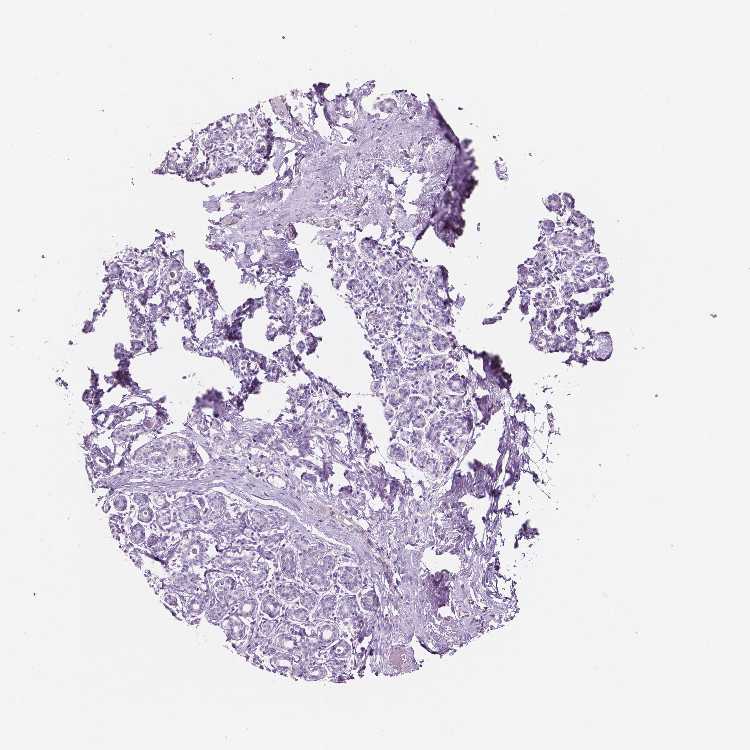

BREAST - Antibody stainingi

Antibody staining in the annotated cell types in the current human tissue is reported as not detected, low, medium, or high, based on conventional immunohistochemistry profiling in selected tissues. This score is based on the combination of the staining intensity and fraction of stained cells.

Each image is clickable and will lead to virtual microscopy that enables deeper exploration of all samples and also displays staining intensity scores, fraction scores and subcellular localization as well as patient and tissue information for each sample.

Antibody HPA063412

Adipocytes Not detected

Glandular cells Not detected

Myoepithelial cells Not detected